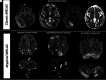

Results: Thirty-five patients with a diagnosis of mitochondrial DNA-based MELAS (median age, 12 years; interquartile range, 7-24 years; 24 female) were eligible for this study. Fifty-three discrete variables were evaluated by an unsupervised cluster analysis, which revealed that two distinct phenotypes exist among patients with MELAS. After experts reviewed the variables, they selected 8 victory-variables with the greatest impact in determining the MELAS subgroups: developmental delay, sensorineural hearing loss, vision loss in the first strokelike episode, Leigh syndrome overlap, age at the first strokelike episode, cortical lesion size, regional brain distribution of lesions, and genetic groups. Ultimately, 2-step differentiating criteria were defined to classify atypical MELAS.

Conclusions: We identified 2 distinct patterns of MELAS: classic MELAS and atypical MELAS. Recognizing different patterns in MELAS presentations will enable clinical and research care teams to better understand the natural history and prognosis of MELAS and identify the best candidates for specific therapeutic interventions.